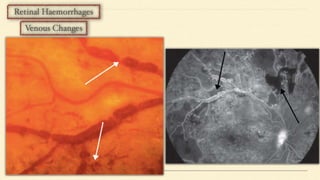

• Micro aneurysms

• Retinal haemorrhages

• Retinal haemorrhage > 20 per quadrant in 1-3 quadrants

• Venous beading

• Intra Retinal Microvascular Anomalies (IRMA)

• Cotton Wool Spots (CWS)

4 - 2 - 1 Rule

• Severe haemorrhage (>20/quadrant) in 4 quadrants

• Venous beading in 2 or more quadrants

• IRMA in 1 or more quadrants